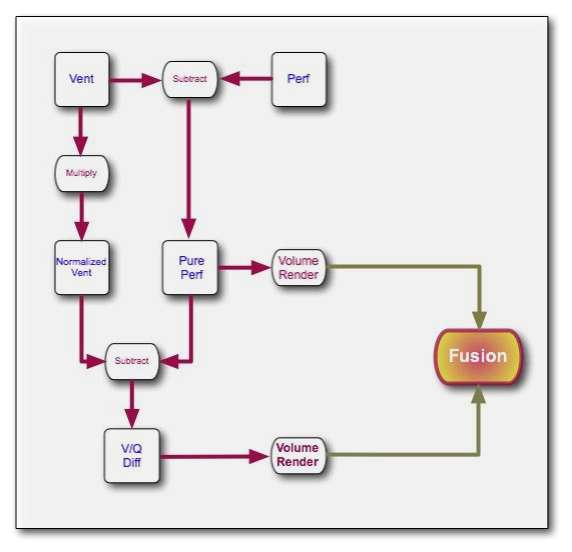

We'll conclude this chapter by considering an application of 3D visualization which integrates many of the image processing techniques we've described in this wikibook. We'll use the two SPECT scans, from a patient's lung-ventilation (V) and lung-perfusion (Q) studies, in an attempt to visualize any mismatch(es) characteristic of pulmonary embolism (PE). The application we'll consider is called subFusion Processing because it involves both image subtraction and image fusion techniques.

Note again that the SPECT studies were generated using a swamping technique where the perfusion scan was acquired immediately following the ventilation scan using an administered activity which generated a relative count rate of about 5:1 between scans. The first image processing step therefore is to correct the perfusion scan for the background ventilation activity.

Since the ventilation tracer in this case was administered using a aerosol, we can assume for simplicity that its biodistribution is reasonably identical in the two scans. Further, since the scans were acquired about 15 minutes apart using the 99mTc radioisotope, we can assume a neglegible effect from radioactive decay. We can simply therefore subtract the ventilation stack from the perfusion stack, on the basis of these assumptions, to isolate what we'll call the "pure perfusion" scan.

The second step is to normalize the two scans by multiplying the ventilation stack by a factor such that the mean counts (for example) in the two stacks are similar.

- We can now compare apples with apples!

Since a PE mismatch is likely to arise from regions of the lungs which contain counts in the ventilation scan and are relatively bereft of such counts in the perfusion scan, we can subtract the "pure perfusion" stack from the ventilation stack, as a third image processing step, to isolate any such differences as positively-valued features.

The final image processing step is to volume render this difference stack along with the "pure perfusion" scan and to blend the results, as illustrated in the following image:

The steps involved are outlined in the following diagram. Note that minor processes, such as CLUT selection, relative opacity adjustment and contrast enhancement are omitted from this diagram for the sake of simplicity. Note also that an image registration step may need inclusion at the beginning of the procedure in cases where patient movement occurs between the two SPECT acquisitions.